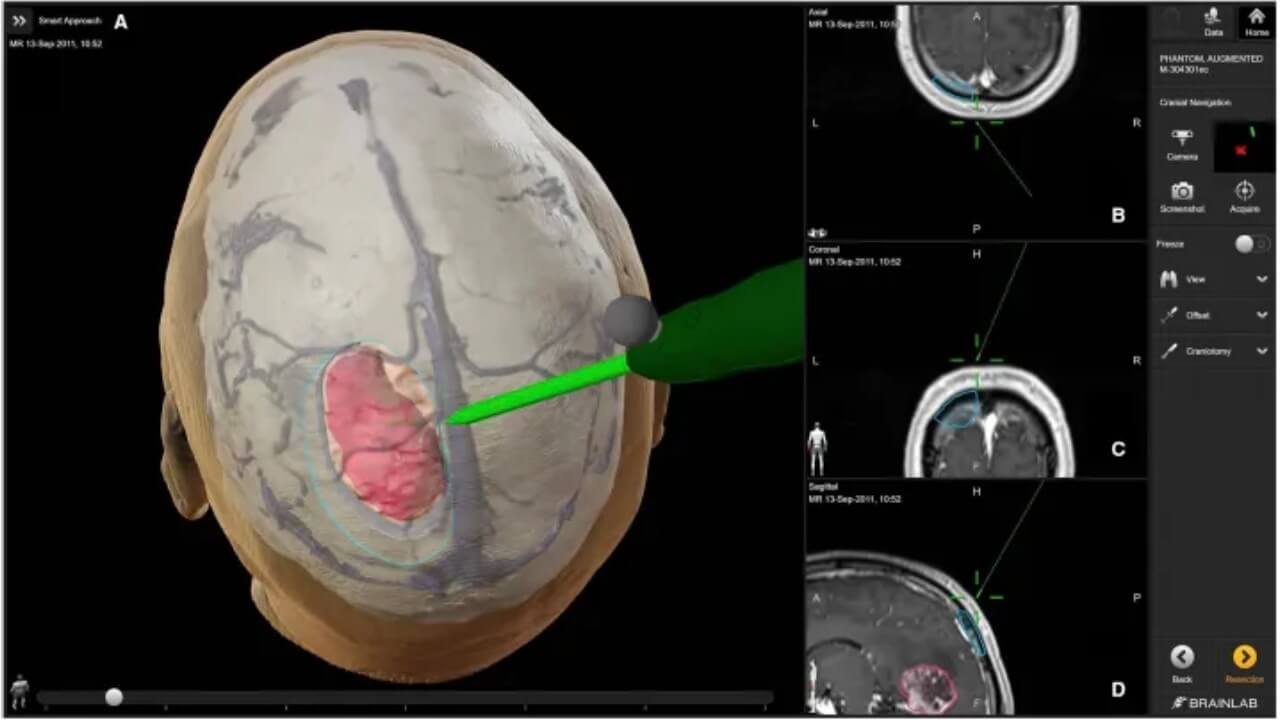

- Neuronavigation systems. It is a modern, important part of any neurological procedure that integrates preoperative MRI or CT scans to create a 3D map of the brain. It helps surgeons precisely plan the surgical path, avoid critical structures, and improve the accuracy of neoplasm removal.